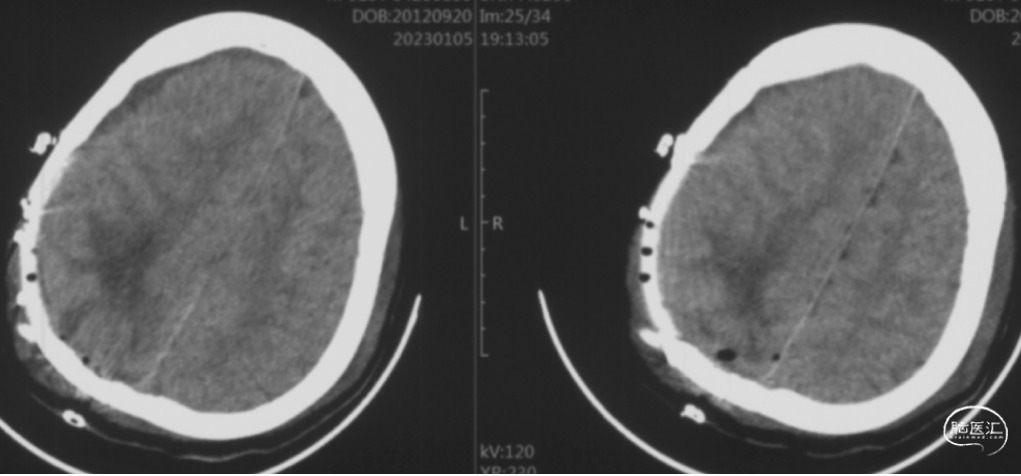

头颅CT

出血时CT,显示右顶叶脑内血肿,右侧脑室受压,中线结构向对侧移位明显。

血肿清除后9天CT,显示右顶叶脑内血肿大部清除,脑室受压及中线结构移位好转。